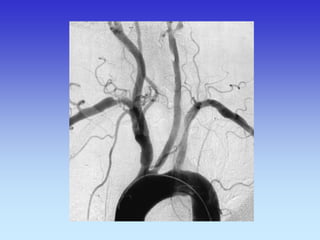

METODE PRIKAZA KRVNIH ŽILA

•UZ-DOPPLER

•DSA

•CTA

•MRA

VASKULARNA OPSKRBA WILLIS-ijev prsten

a. cerebri ant.

a. cerebri media

a. cerebri post.